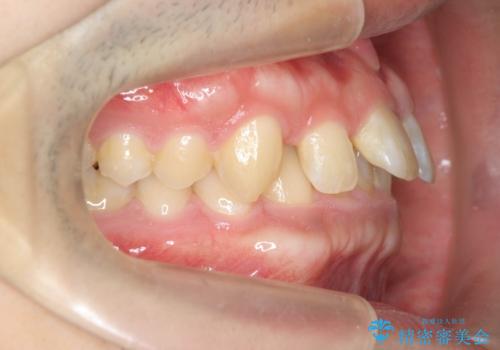

ディープバイトのマウスピース矯正

- 飛び出してしまい、隙間のある前歯をきれいに並べたい、と矯正治療を希望され来院されました。

上顎前歯を後方に引き、隙間を閉じるためには下顎前歯の絶対的な圧下を行い、深い噛み合わせを改善することが必要です。

圧下は歯の動きの中でも難しい動きの一つで時間がかかることが多いです。

前歯でチューイーをしっかり噛み、咬合圧を伝えたことで下顎前歯が圧下し、上顎前歯の隙間を閉じることができました。